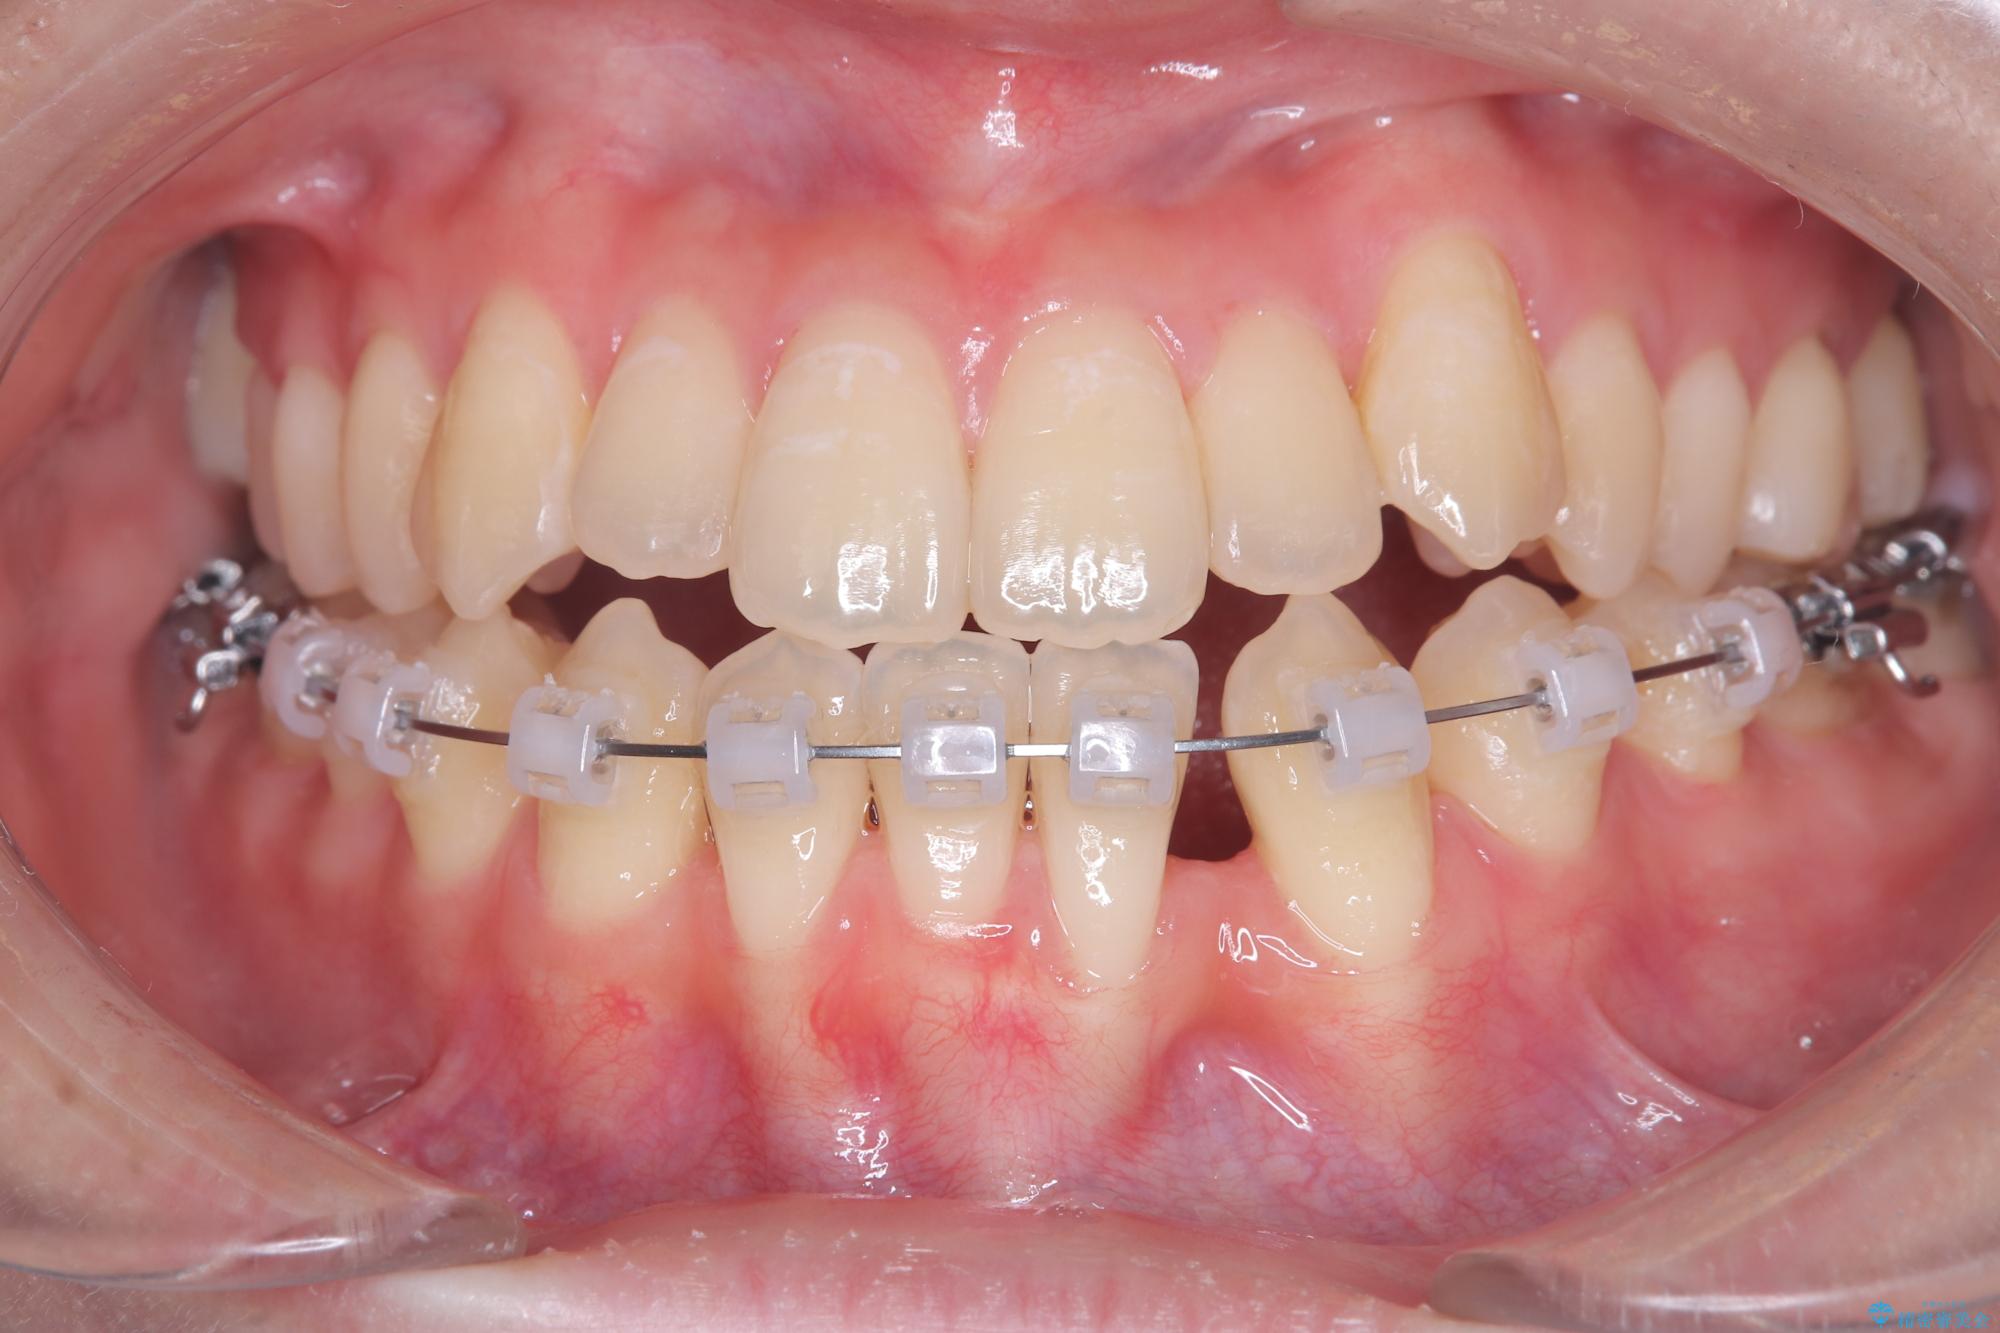

安全かつ確実に抜歯スペースを閉じ、咬み合わせを完成させるため、マウスピースから**ワイヤー矯正(マルチブラケット装置)**へ切り替えるリカバリープランを提案しました。

装置の変更と歯肉への配慮: ワイヤー矯正は歯の根(歯根)を平行に移動させる「歯体移動」を得意としています。本症例では、歯肉退縮を防ぐために、歯の傾きを精密にコントロールしながら抜歯スペースを閉じる必要がありました。ワイヤー装置を用いることで、インビザラインでは難しくなっていた三次元的な細かい調整を可能にしました。